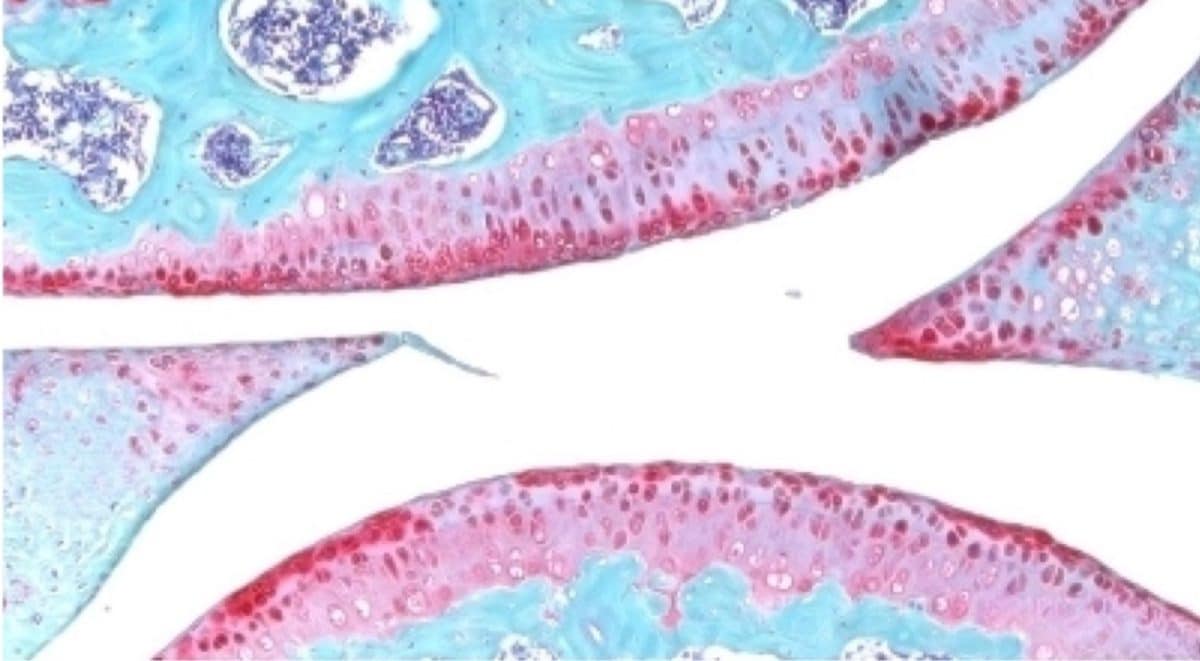

Ученые проверили разработку на образцах человеческой ткани после операций по замене коленного сустава. Эти образцы включали внеклеточный матрикс в суставе и клетки хондроцитов, генерирующие хрящ. Они отреагировали на лечение, образуя новый, функциональный хрящ.

Белок 15-PGDH, также известный как герозим, — это фермент, который с возрастом становится более активным. Этот фермент обнаружили эти же исследователи в 2023 году. Белок также приводит к потере функции тканей. Заблокировав функции 15-PGDH с помощью небольшой молекулы, исследователи выяснили, что это приводит к увеличению мышечной массы и выносливости старых животных. Экспрессия 15-PGDH у молодых мышей, напротив, привела к сокращению и ослаблению их мышц. Герозим также участвует в регенерации костей, нервов и клеток крови.

Результаты исследования показали, что можно регенерировать хрящ, потерянный из-за старения или артрита, с помощью перорального препарата или местной инъекции. Это избавляет пациентов от замены коленного и тазобедренного суставов. Препарата сейчас находится на стадии клинических испытаний.